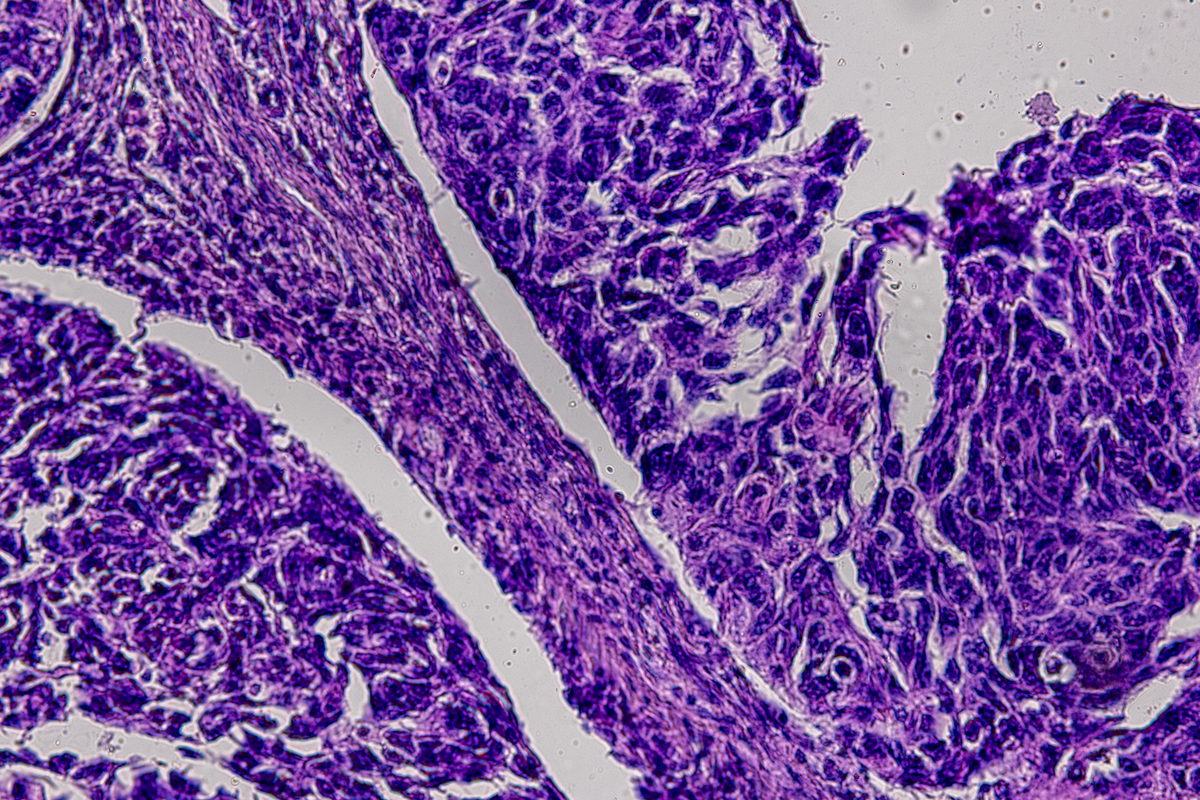

为了避免排斥反应,我们使用了自体绵羊肝脏。去细胞化的胎盘提前存储。为了适应腹股沟区域的移植物并避免血管“偷窃”现象,在与股动脉血管吻合之前,修剪了多余的胎盘组织(支持图S7)。我们在移植后的1、5-7、14-15、20、30和45天检查了肝化胎盘(每个1-2个,共计10个)(支持表1)。在肝脏获取过程中,没有绵羊因肝脏切除而丧命。在某些情况下,通过铸件验证了肝化胎盘的灌注情况(图2A)。乳胶进入肝化胎盘并出现在肝组织中。通常情况下,我们在绵羊肝脏获取后的25-60分钟内移植肝化胎盘。在血管吻合后立即,移植物灌注良好,没有过度膨胀或破裂。随后,移植物产生了可见的腹股沟突出。移植肝化胎盘没有引起任何疾病或死亡。在移植后的1、10、15和45天评估显示胎盘和股动脉血管吻合处均健康。移植后1天的组织学显示胎盘叶和血管充满了血液(图2B)。随后,组织融合形成了连续的肝脏片,其中包含肝细胞和窦道,窦道中含有血液和其他细胞,周围由胎盘叶的结缔组织基质所包围,其他细胞类型也寄居在胎盘囊内。